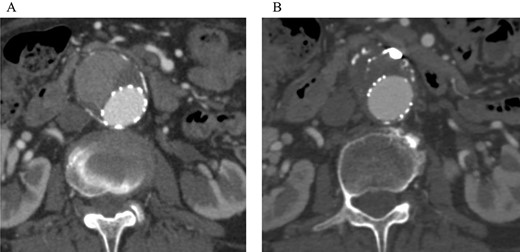

Post-embolization CT demonstrated that the sac shrank with no evidence of a continuing endoleak. (A) Pre-embolization CT showed a contrast effect in the sac. (B) Post-embolization CT showed no contrast effect in the sac.